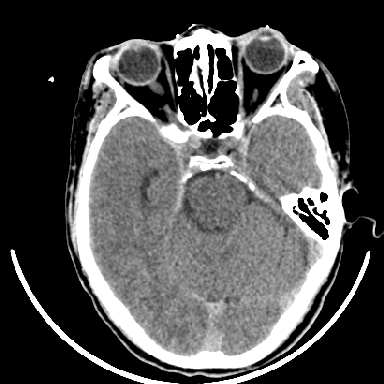

标题: CT6056:脑出血(血管畸形?) [打印本页]

标题: CT6056:脑出血(血管畸形?)

m 40突发头痛左侧偏瘫3小时

考虑高血压性脑出血,依据:

1是高血压性脑出血的好发部位,形态呈肾形,是高血压性脑出血的常见形状

2增强时占位效应加重了,考虑出血还没有停止

3病灶周围水肿不是太厉害,一般肿瘤出血水肿多非常明显

4病灶周围的‘软组织’影没有明显的强化

5至于脑血管畸形引起的出血,暂时没有看到明显的畸形血管影,也不太支持

支持右侧基底节脑出血

右侧基底节区脑出血.

支持右侧基底节区(主要为外囊区)原发性脑出血。

另附部分资料:“血液溢出血管外形成血肿,其内含有大量血红蛋白、血浆白蛋白,球蛋白,因这些蛋白对x线的吸收系数高于脑质,故ct呈现高密度阴影,ct值达40~90h,最初高密度灶呈非均匀一致性,中心密度更高,新鲜出血灶边缘不清。基底节区血肿多为“肾”型,内侧凹陷,外侧膨隆,因外侧裂阻力较小,故向外凸,其它部位血肿多呈尖圆形或不规则形”

术中抽出40ml陈旧血液,血肿底部似见一条索血管影